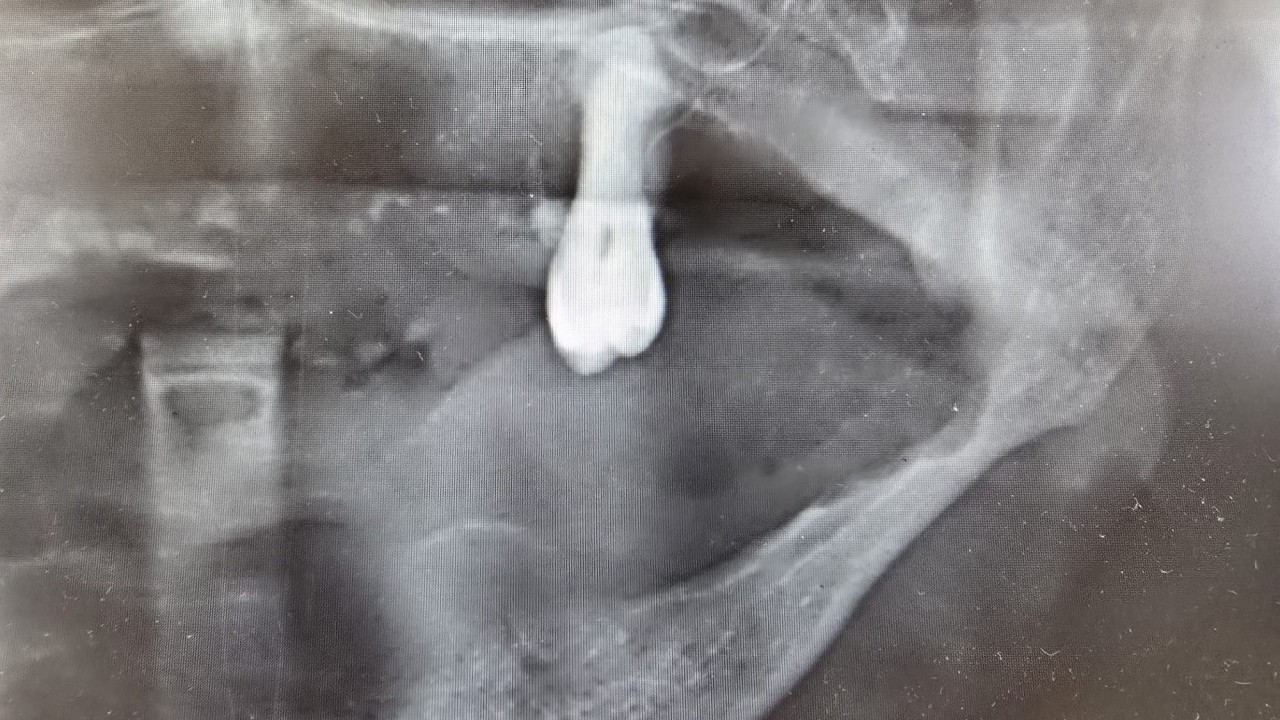

Sebepsiz yere dişlerin sallanması, uyuşukluk olması, yüzde sebepsiz ağrıların, çene bölgesinde sebepsiz ağrıların oluşması kanserlerin başlangıç bulguları arasındadır. Zaten kanserlerin en fazla oluştuğu yerler ağız içerisinde dilin özellikle arka kenarlarıdır. Bunlar ne yazık ki başlangıçları da ağrısız olduğu için bir kısmının gözden kaçabilmekte. O yüzden insanlarımızdan, halkımızdan bu konuda dikkat etmeleri, eğer böyle bir lezyonla muhatap olurlarsa mesela bir yakınından ağız içerisindeki görüntüsünü çekmesini talep etmeli. 2 hafta sonra da aynı şekilde bu görüntü duruyorsa veya daha da büyümüşse en yakın merkeze gitmesini önermekteyiz” ifadelerini kullandı.